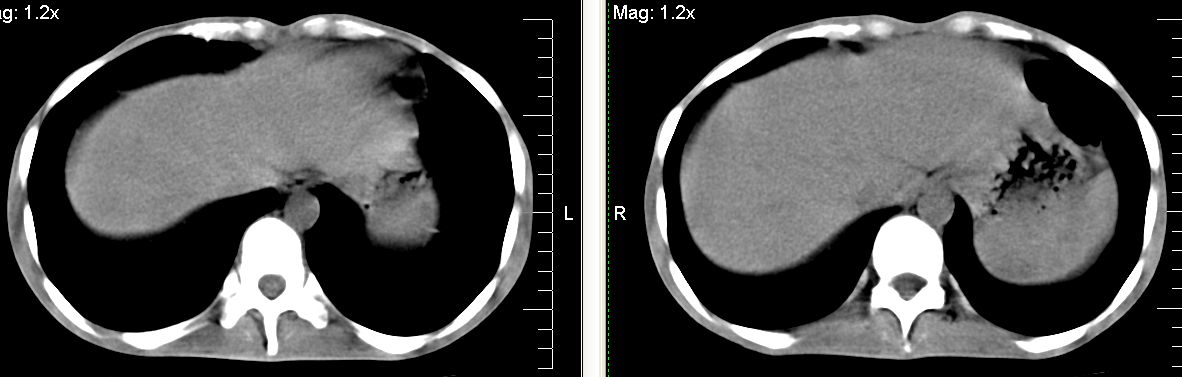

m 29 肺tb患者,目前诉下腹疼痛 t39度 腹韧,有压痛,可触及3x4cm包块

脾脏多发类圆形低密度影,建议增强扫描。

脾脏多发类圆形低密度影并腹水,建议增强扫描。

脾脏多发低密度灶,肠系膜及腹膜后见多发大小不等结节状影,右结肠旁沟见低密度影,结合病史考虑:脾结核,肠系膜及腹膜后淋巴结结核,少量腹水。